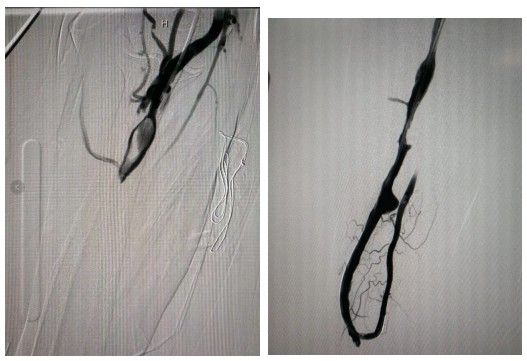

李威主任决定在超声联合数字减影血管造影(DSA)引导下进行操作,可以更迅速直接的看到动静脉内瘘血管狭窄程度以及上方血管的情况。4月10日上午11点手术开始,常规消毒、局部麻醉、穿刺,采用导管导丝技术找到完全闭塞的瘘口,造影确认后送入球囊、逐段扩张,球囊撑开血管狭窄的部位。刚开始加压扩张后很快就会被弹回,反复经过两次后感觉明显好了许多,李威主任用手搭在李金凤的内瘘血管上,已经可以触摸到轻微的震颤了。术中复查造影,李威主任发现李金凤血管里还有很长一段血栓。“就像一条塌方的隧道,里面被堵住的情况看不清楚,我们只能凭借多年的介入手术经验和手感将血栓一点一点取出。”术后李威主任在回忆时说。反复抽吸出大量血栓后,经再次造影确认血流通畅,李威主任拉过李金凤的左手放到右手臂内瘘处说:“摸到了吗?你的内瘘已经恢复震颤了。”在经历了3天的内瘘闭塞后,李金凤终于又触摸到了内瘘的震颤,耳边也隐约听到内瘘传来的隆隆声。整个置管取栓联合球囊血管成形术历时近2个小时,非常成功。术后返回病房,李金凤看着针尖样的“手术刀口”,触摸着恢复震颤的内瘘,长舒一口气:“这条‘生命线’保住了,今天终于可以睡个安稳觉了。”

导丝介入术中影像

术前完全闭塞 术后恢复畅通